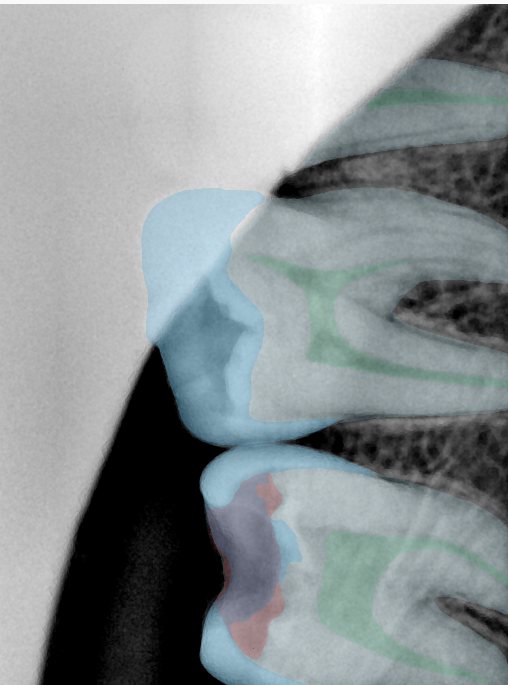

CR/DR 牙齿分割阶段记录

当前进展

- 完成了 CR/DR 牙齿相关分割训练

- 当前结果已经达到阶段预期,但仍有细节问题需要继续处理

相关测试

遇到的问题

- 训练过程中出现过 mask 下移问题

- 部分结果会出现 box 填充异常

- mask 边缘仍然有比较明显的锯齿感

参考

第二版算法问题测试